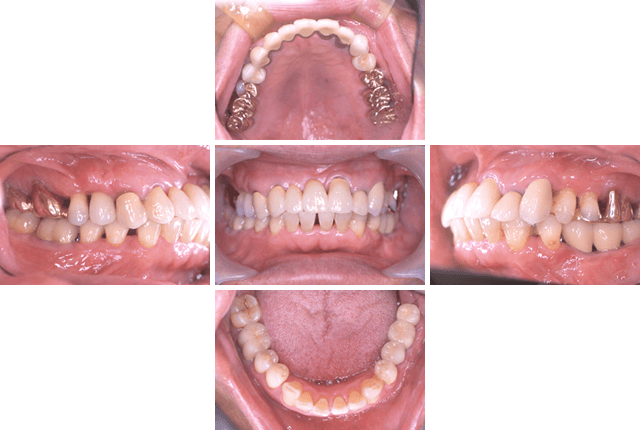

失われた歯の数、インプラントを埋め込む骨の硬さ、大きさ、位置により、治療法にはさまざまな選択肢があります。歯にかかる力の方向や強さはもちろん、患者さんに無理のない衛生管理などを含め総合的に検討した上で、治療計画が立てられます。

当院では、幅広いケースや症例に対応したインプラント治療法を導入しております。

「骨の量が足りないので難しいと言われた」「あごの骨を削りたくない」「手術が怖い」などの理由で治療を諦めていた方も、ぜひ一度当院にご相談ください。

あごの骨が痩せてしまって、インプラントが行えない…。上のあごの難症例などあらゆる症例に対応可能です。ドリルを殆ど使わないので骨を損なわず、歯ぐきも最低限しか切らずに済むため、処置後の経過が良く、負担を最小限に出来ます。